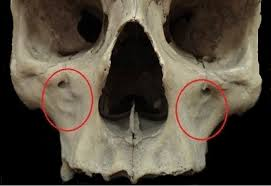

If it is lower down on the maxilla as the first two images suggest then it would be easier to check but just sticking your finger in your mouth and feeling if the bone above your teeth slants back slightly

If it is lower down on the maxilla as the first two images suggest then it would be easier to check but just sticking your finger in your mouth and feeling if the bone above your teeth slants back slightly